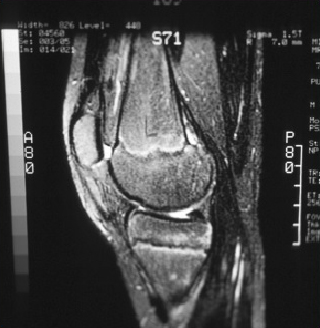

[Figure caption and citation for the preceding image starts]: Magnetic resonance imaging (MRI) of knee demonstrating healingFrom the collection of H. Chambers, MD [Citation ends].